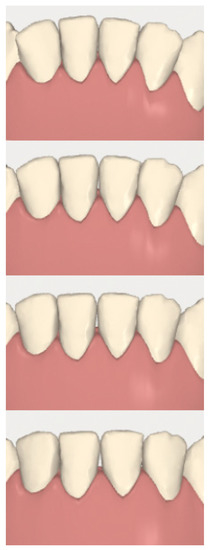

2.3.1. Example—Anterior Open-bite

2.3.2. Example 2—Extraction Space Closure